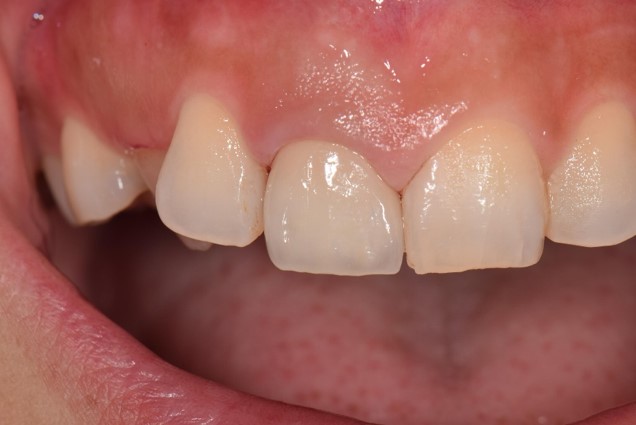

拡大した様子はこちら